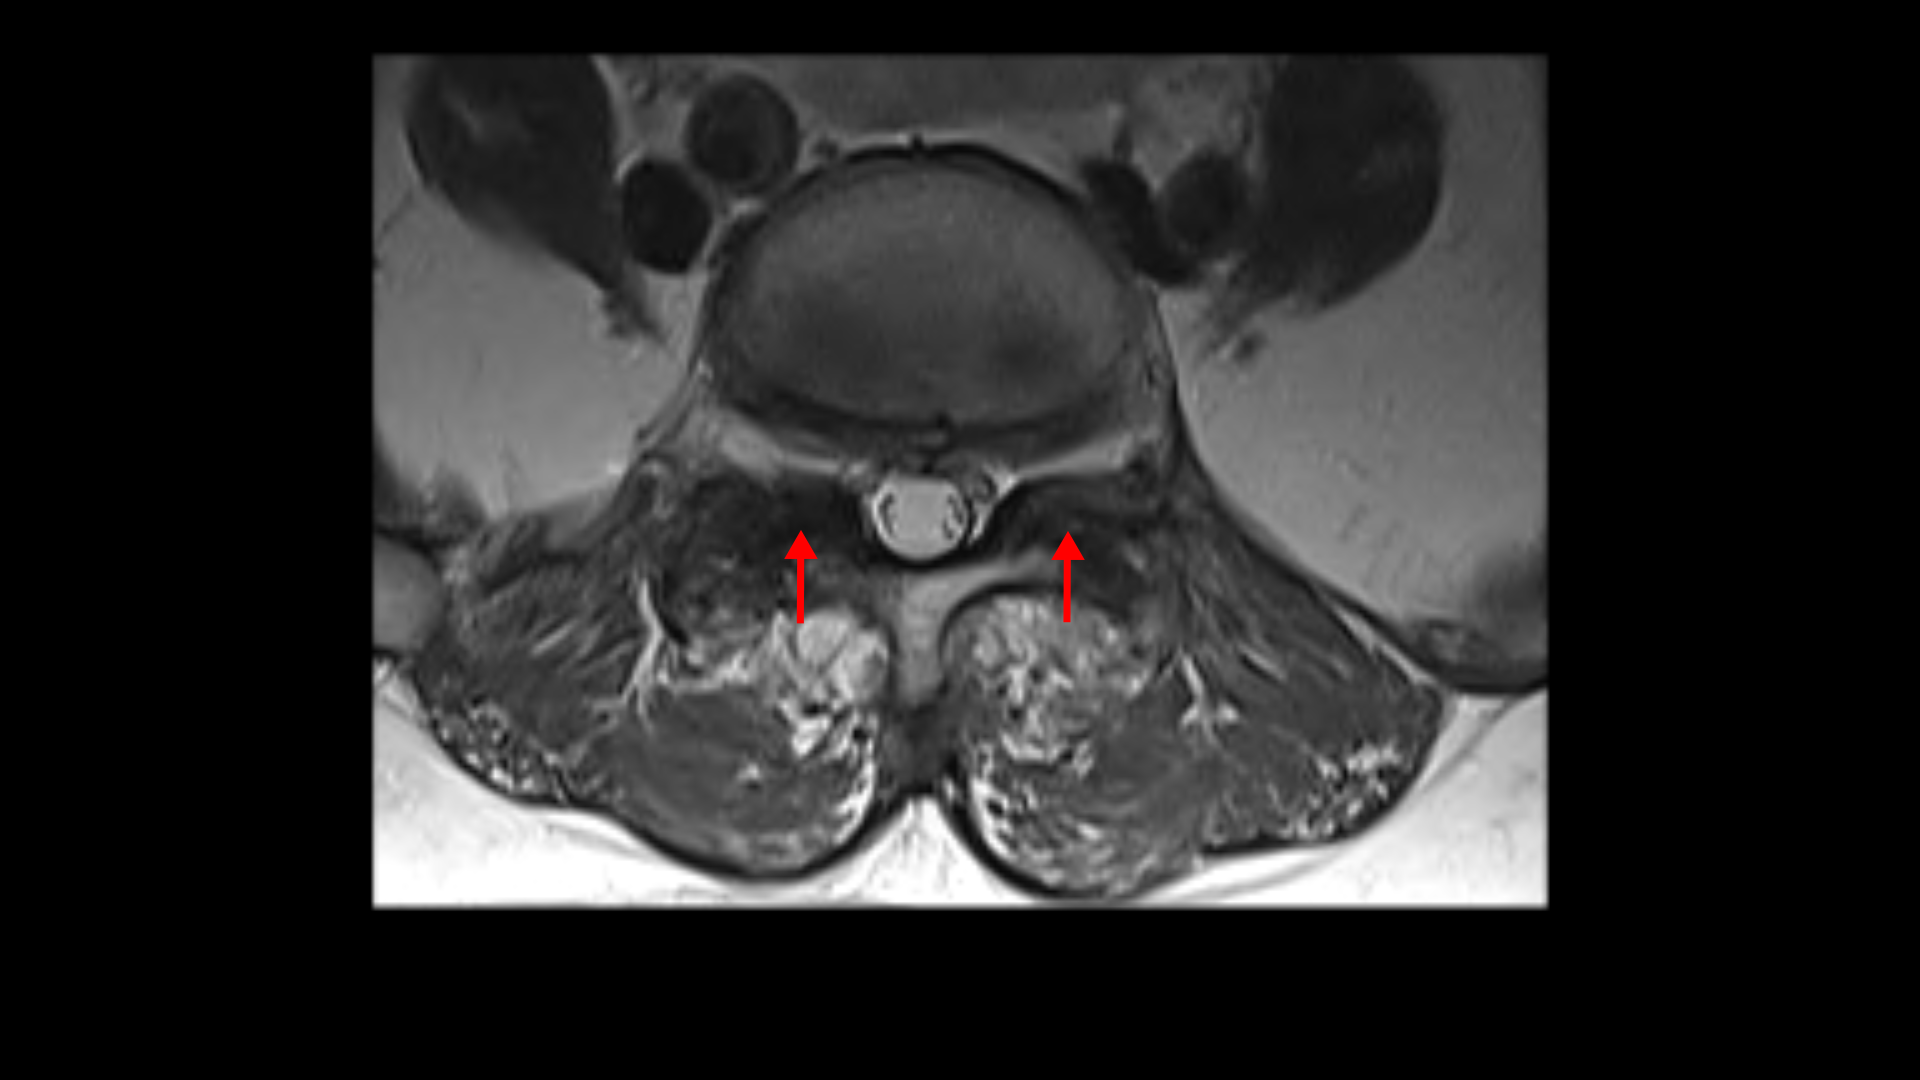

우선 이 환자분의 X-ray를 보면 5번 1번에 전방전위증으로 인한 불안정성이 있습니다. 척추가 불안정하므로 전방전위로 뼈가 밀려 나간 정도가 MRI에 보이는 것보다 X-ray 굴곡상태에서 보는 게 훨씬 더 심해 보입니다. 또 척추 여러 마디에 퇴행성 병변이 보입니다.

먼저 5번 1번에 척추관 내의 황색인대의 골화 현상이 보이고

후관절의 퇴행도 심해 보입니다.